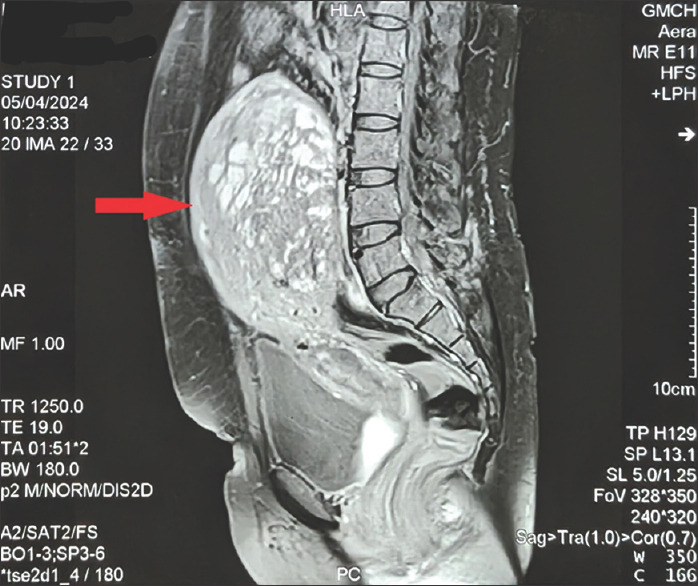

Cystic adenomyosis, a rare variant of adenomyosis, poses diagnostic challenges due to its resemblance to other uterine pathologies. We present the case of a 37-year-old multiparous woman with a history of cesarean sections, who presented with heavy menstrual bleeding and progressive pelvic pain. Despite initial medical management, symptoms persisted, prompting further investigation. Ultrasonography initially suggested fibroid degeneration or a neoplastic change, later confirmed by magnetic resonance imaging which showed degenerative changes in fibroid. However, worsening symptoms and failed medical management led to surgical intervention. The patient underwent a total abdominal hysterectomy, revealing cystic spaces filled with altered blood within the myometrium. Histopathological analysis postsurgery confirmed the diagnosis of cystic adenomyosis. This case highlights the diagnostic challenges and therapeutic considerations in managing cystic adenomyosis in multiparous women.